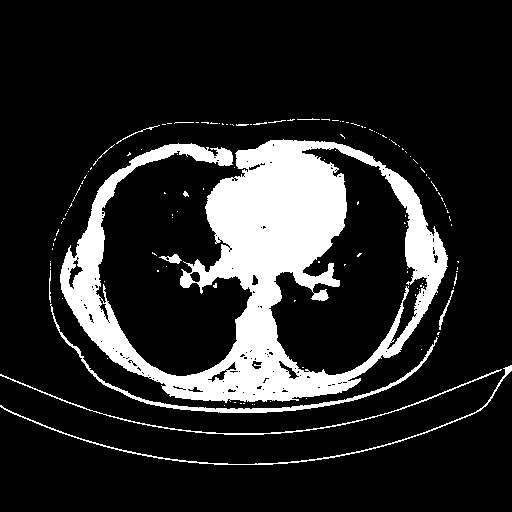

Image Grid

4Γ—3 grid: Rows show different image types (Original NATIVE, Reconstructed NATIVE, Original VENOUS, Generated VENOUS), Columns show windowing techniques (No Window, Lung Window, Mediastinum Window)

Original NATIVE CT scan (input)

Full window (WL 1023.5, WW 4095 β†’ Low βˆ’1024, High +3071)

Actual HU range: [-1024.0, 3071.0]

Reconstructed NATIVE CT scan (cycle consistency)

Original VENOUS CT scan

Generated VENOUS CT scan (A→B translation)